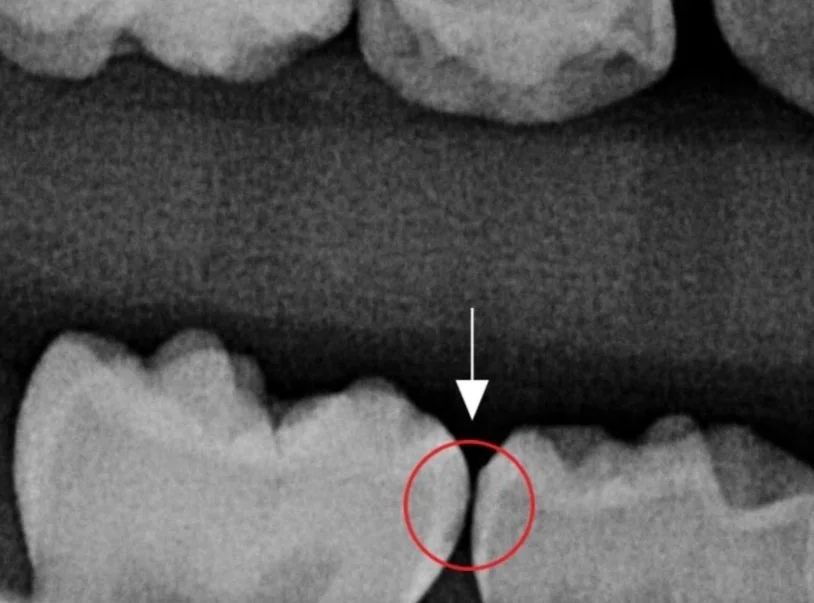

Teeth treated with SDF and decay arrested